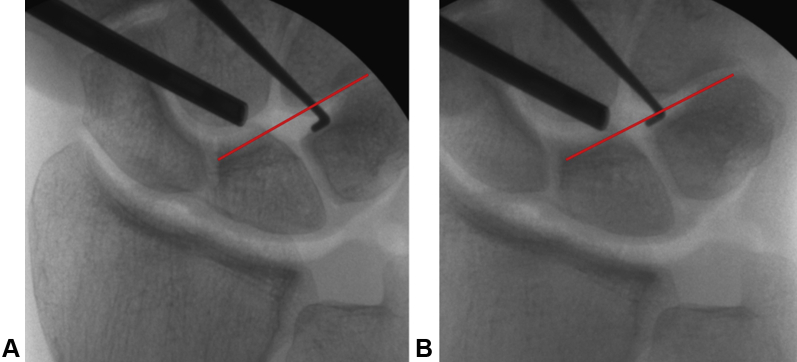

One example of a clinical case is a 33-year-old man who sustained a bicycle accident 1 year before surgery. A stressed x-ray showed malrotation of the LT joint as well as a lesion of the palmar part of the LT ligament. He had pain with rotation and weight-bearing. The diagnosis was confirmed arthroscopically and under an image intensifier (Fig. 5). A reconstruction was performed; 3 months later, the compression screw was removed after healing of the graft was confirmed (as is typically done). So as not to manipulate the joint further, the cortical screws were left in situ. The patient returned to work without pain when rotation the arm and bearing weight upon it. After 6 months, at the final follow-up, the Disabilities of the Arm, Shoulder, and Hand questionnaire score improved from 69.8 to 36.2 and the final Michigan Hand Outcomes Questionnaire score was 77.6. The final grip strength improved to 40.5 from 30 kg before surgery.

Figure 5.

Clinical case: A 33-year-old man with an LT injury and instability on arthroscopic and radiologic examination. A Pressure application leading to widening of the LT joint. B Without pressure, return to normal alignment.